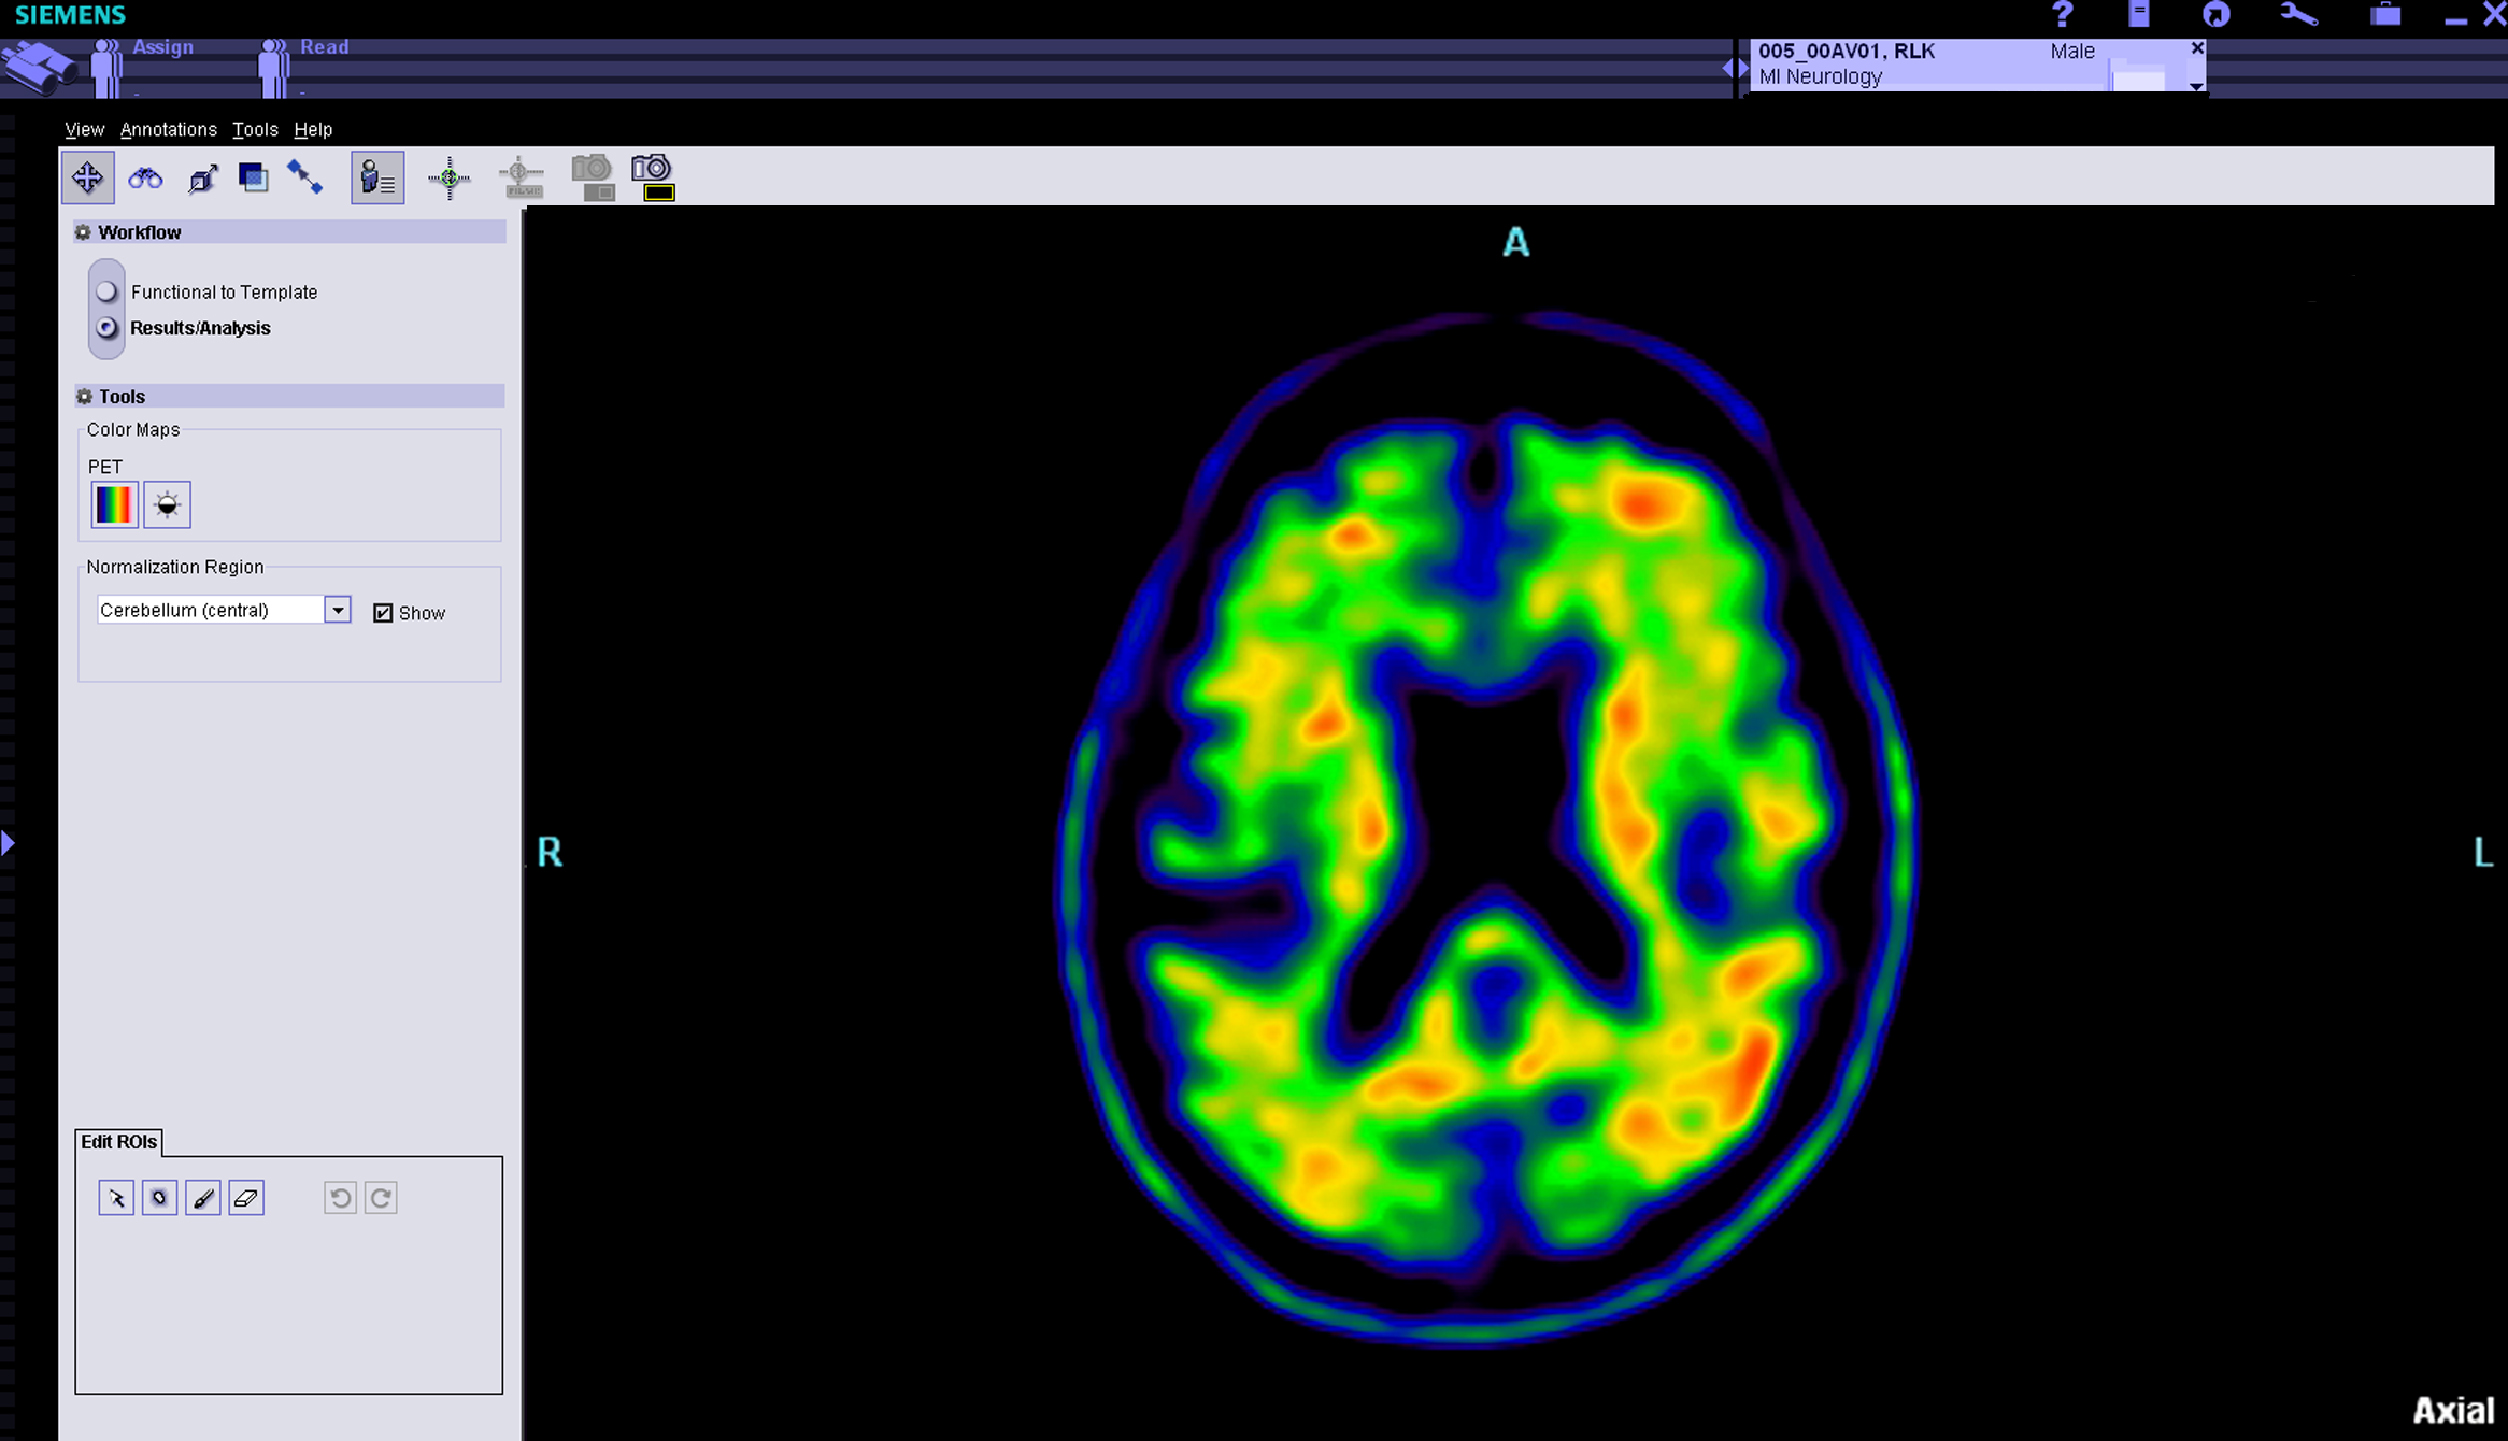

The study matches changes in clinical and cognitive testing with Alzheimer’s-related changes in biological markers detected in blood, cerebrospinal fluid and DNA samples donated by volunteers. Brain scans identify changes in brain volume, white matter integrity, functional connectivity between brain regions, glucose metabolism and the buildup of amyloid protein plaques — a hallmark of the disease. ADNI3 will add brain scans that detect tau protein tangles, another indicator of the disease. Blood, cerebrospinal fluid and DNA samples also enable scientists to better understand Alzheimer’s-related chemical changes and how genes influence the disorder.

- The use of tracers that image tau protein tangles — a significant indicator of Alzheimer’s disease — in the living brain. Researchers will gain new insights into how and where the protein builds in the brain, and how it may interact with amyloid protein plaques to drive disease progression;

A key feature of ADNI has been its focus on collaboration and rapid data sharing. To speed the pace of analysis and findings, ADNI investigators make their collected data widely available; the study has been used in over 1,200 research papers. MRI and positron emission tomography (PET) scan brain images as well as clinical, genetic and fluid biomarker data are available to qualified researchers worldwide through a web-based database. To date, more than 8,500 researchers have sought access.